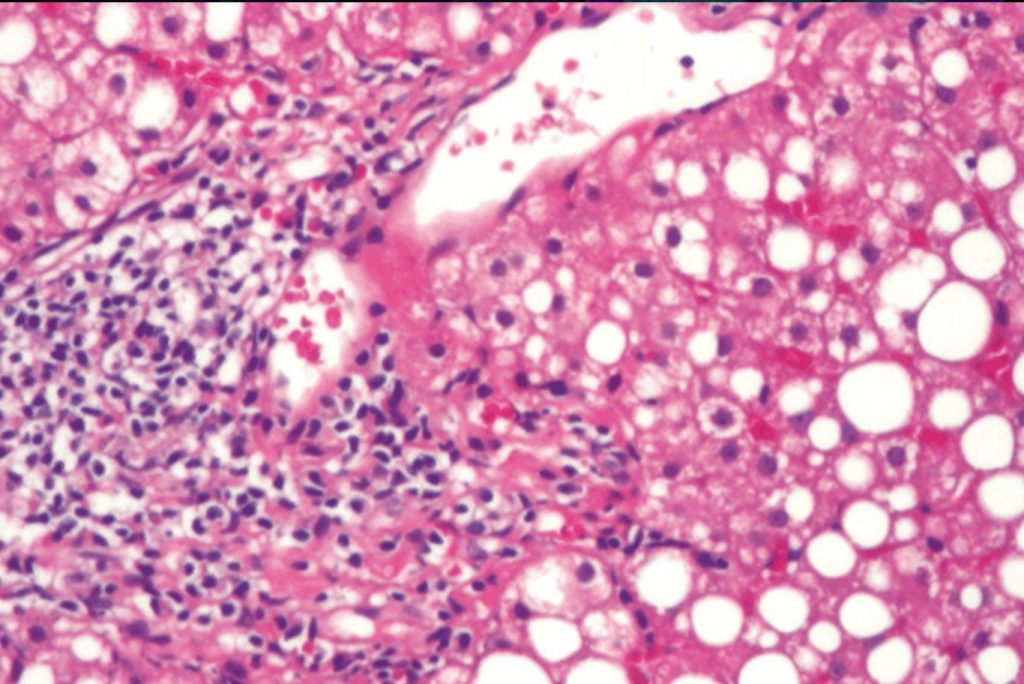

D-galactosamine is known to cause acute liver damage in animal models. The mechanism of D-galactosamine hepatotoxicity is not fully understood but D-galactosamine is believed to cause an intracellular deficiency of uridine metabolites leading to acute liver failure10. As illustrated in Figure 1, acute liver injury by D-galactosamine is associated with waste accumulation, systemic inflammation and impaired regeneration. These three problems are also seen in humans and often contribute to death after drug induced acute liver injury which makes the porcine model of D-galactosamine acute liver failure an appropriate large animal model for testing extracorporeal liver assist devices.